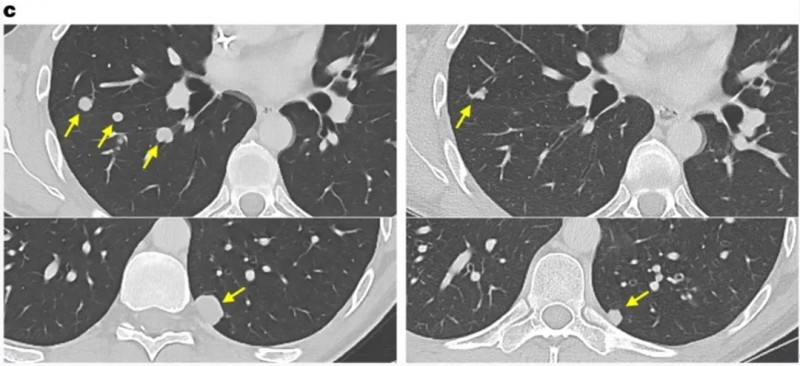

最后一位结肠癌患者,在治疗7个月时,右肺、左肺两处结节完全消退,其余结节也有所缩小。

▲图源“Nat Med”,版权归原作者所有,如无意中侵犯了知识产权,请联系我们删除